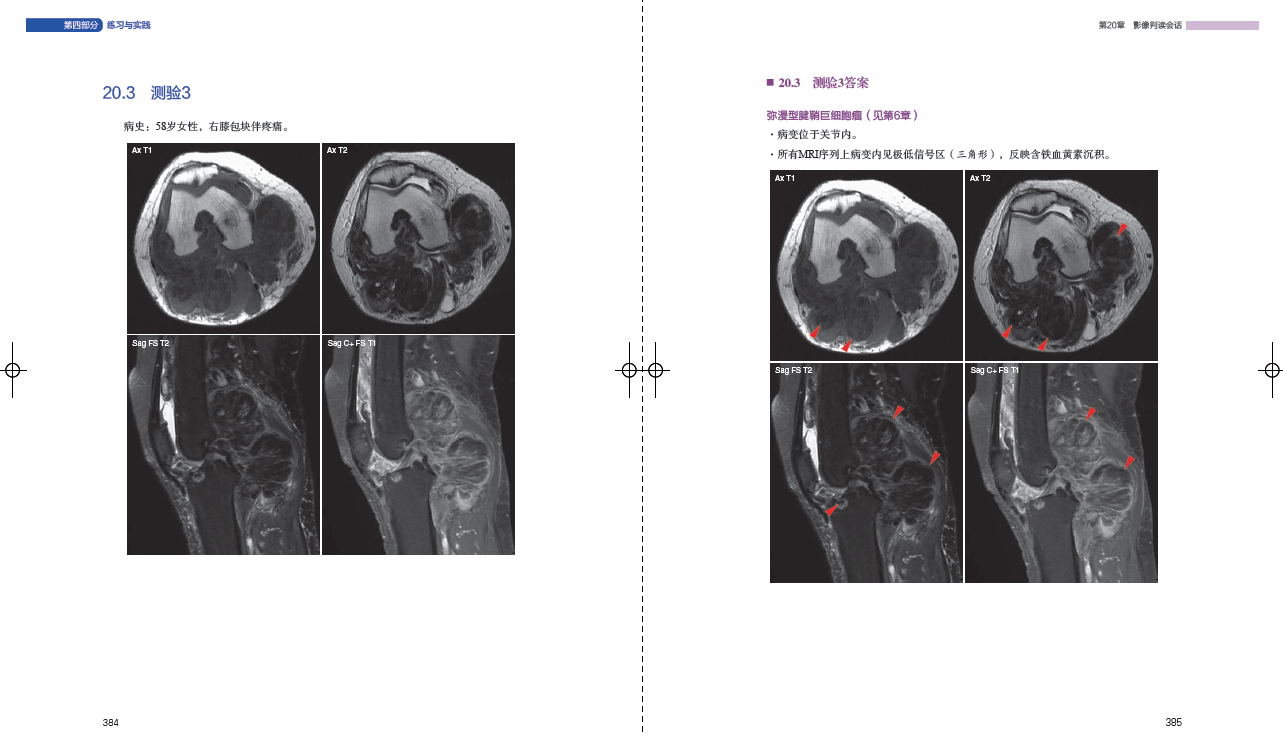

203 测验3384

2021 测验21420